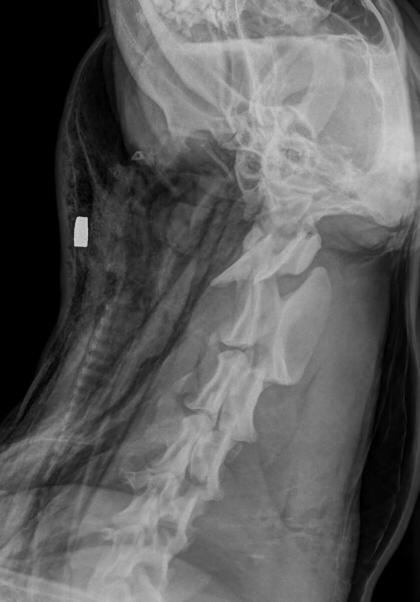

Na segunda-feira (22), o cão foi avaliado pelo médico veterinário Laerte Lanznaster de Quadros Filho, que percebeu que o inchaço se tratava de ar subcutâneo. “Comecei a apalpar e foi onde percebi uma lesão arredondada no lado esquerdo do pescoço. Encaminhei para radiografia e no exame foi possível ver a estrutura metálica similar a um projétil”, conta o veterinário.

Com o exame em mãos, a principal suspeita do veterinário era uma ruptura de traqueia. Um procedimento para drenagem do ar embaixo da pele foi realizado para que o local exato da perfuração pudesse ser localizado.

Após a morte do cão, foi feita a necropsia para retirar o projétil e foi possível perceber um extenso hematoma na região do pescoço do cão. Além disso, foi possível determinar que a bala entrou pelo lado esquerdo e se alojou no lado direito do pescoço dilacerando a traqueia.